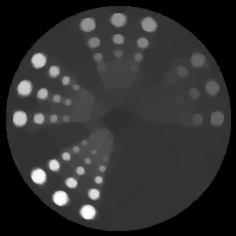

The quantitative results in Fig. 8 in terms of both distance to saddle point and objective value show that randomization speeds up the convergence so that both SPDHG and the algorithm of Pesquet&Repetti are faster than the deterministic PDHG. Interestingly, while more subsets make SPDHG faster, this does not hold for the algorithm of Pesquet&Repetti where the speed seems to be constant with respect to the number of subsets. Moreover, the plot on the left confirms the linear convergence as proven in Theorem 6.1. The visual results in Fig. 8 confirm these observations as SPDHG with 50 subsets and 10 epochs is (in contrast to PDHG) visually already very close to the saddle point.

7.4 PET Reconstruction (Linear Rate)

For the final example we turn back to PET reconstruction but this time with linear convergence rate. This means we want to solve the same minimization problem as in the first example, but now we replace the Kullback–Leibler functional by its modified version as in the previous example. We note again that this does not change the solution of the minimization problem. Moreover, to make TV strongly convex we add another regularization term to . Note that the proximal operator of TV (indeed any functional) with added squared -norm, i.e. , can be solved by means of the original proximal operator . The regularization parameters are chosen as and .

Results